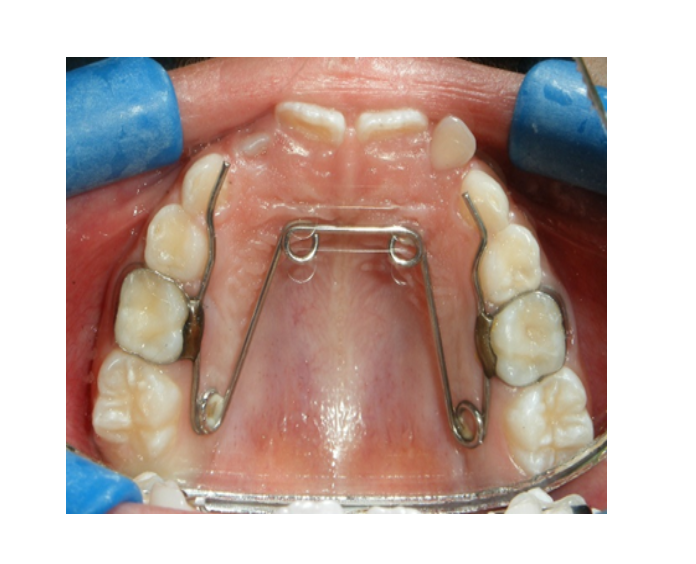

Ortodoncia

temprana